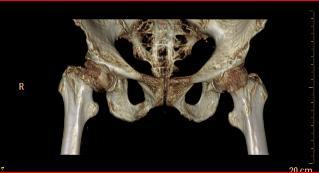

术前四维重建

阿婆姓廖,家住坪地街道坪东社区,今年已经是101岁高龄。日前在家中不慎摔倒,由家属呼叫120救护车紧急送入区六院骨科,被确诊为右股骨颈骨折。